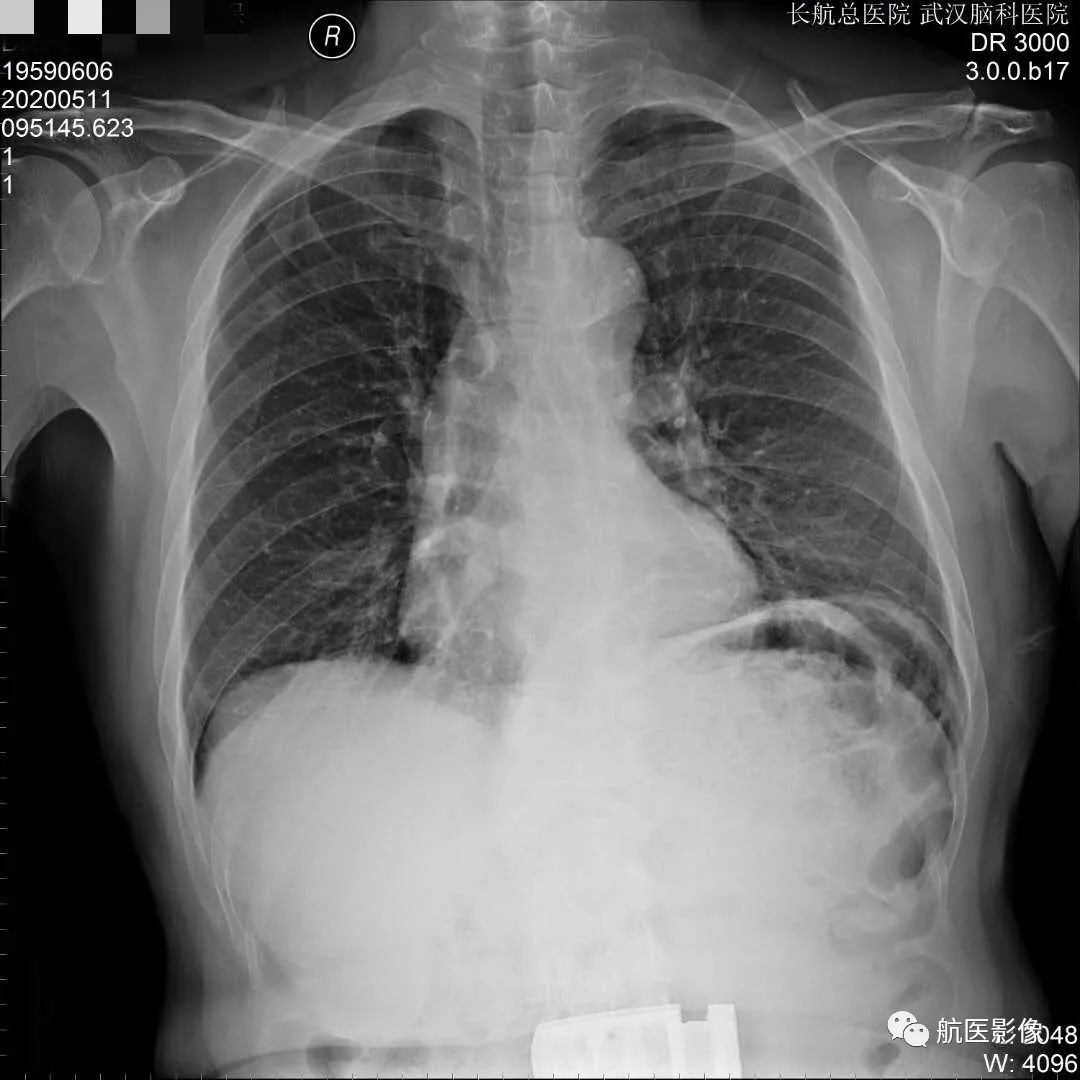

因此多层螺旋CT扫描及三维重建成像在诊断肋骨骨折方面比胸片具有明显优势,特别是靠近胸椎的胸肋关节处及无明显移位的骨折。请注意大多数肋骨骨折的原因是车祸及意外事故,其中很多都涉及到司法鉴定,能够准确诊断肋骨骨折及合并症就显得格外重要。对于急诊的胸部外伤,特别是复合伤患者,多层螺旋CT扫描及三维重建成像,能在极短时间内一次扫描完成,准确诊断肋骨骨折及合并症,可避免胸片检查中需变换体位而造成病情加重,为临床治疗赢得宝贵时间,同时也避免不必要的医疗纠纷。对于胸片怀疑骨折、涉及纠纷且胸片未见明确骨折、胸部外伤临床症状重者均需做多层螺旋CT扫描及三维重建成像,这能为患者提供准确的诊断及治疗,并保护患者的合法权利。

多层螺旋CT扫描及三维重建成像能快速、准确地显示肋骨骨折及合并症,不仅大大减少骨折的误诊、漏诊,还可以为司法鉴定提供更加准确、可靠的客观资料;多层螺旋CT扫描及三维重建成像技术组合对肋骨骨折的诊断较常规的胸片提供更加丰富的影像信息,能显示肋骨骨折位置、形态、数量及合并症,在对肋骨骨折诊断中具有不可替代的优势。